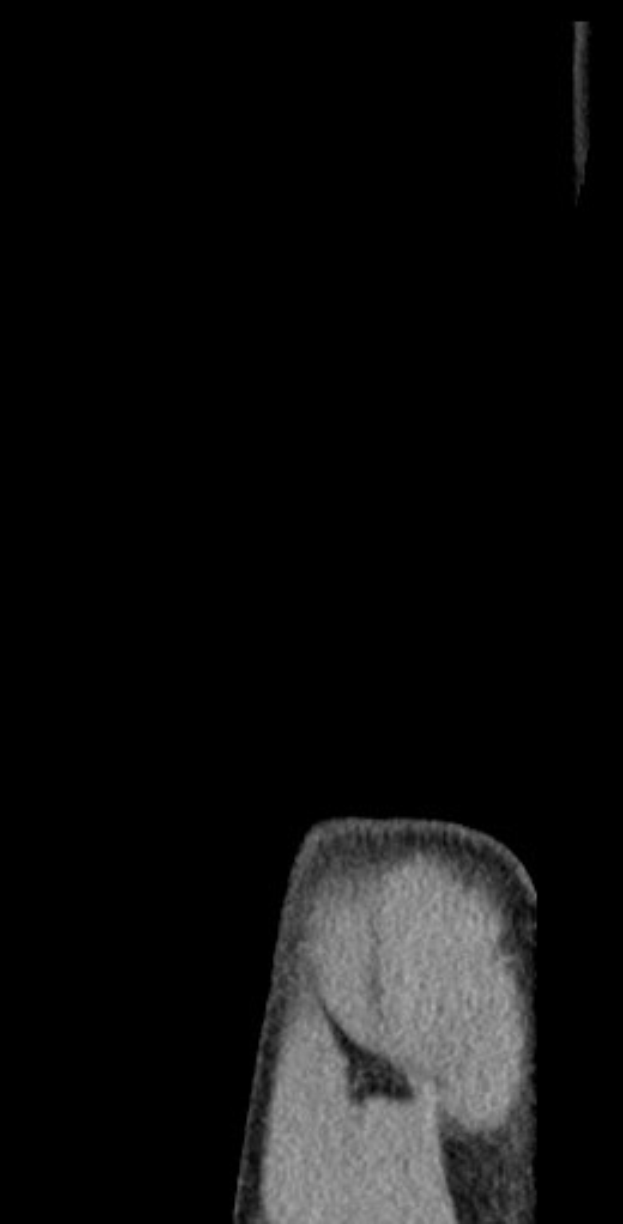

Gechters Schulterprobleme traten erneut während des U21-Länderspiels auf, in dem er wegen Schmerzen vom Platz musste. Eine sofortige Diagnose blieb aus, weshalb Hertha BSC nun eine MRT-Untersuchung angesetzt hat, um das Ausmaß der Verletzung zu klären. Bereits in der vergangenen Saison hatte der Innenverteidiger eine längere Pause wegen eines ähnlichen Schulterproblems einlegen müssen – genaue Details zu seiner damaligen Ausfallzeit sind jedoch nicht bekannt.

Die medizinische Abteilung von Hertha BSC zeigt sich besorgt über Gechters wiederkehrende Schulterbeschwerden. Der Verein wird die MRT-Ergebnisse abwarten, bevor eine endgültige Entscheidung über seinen Einsatz gegen Dynamo Dresden fällt.